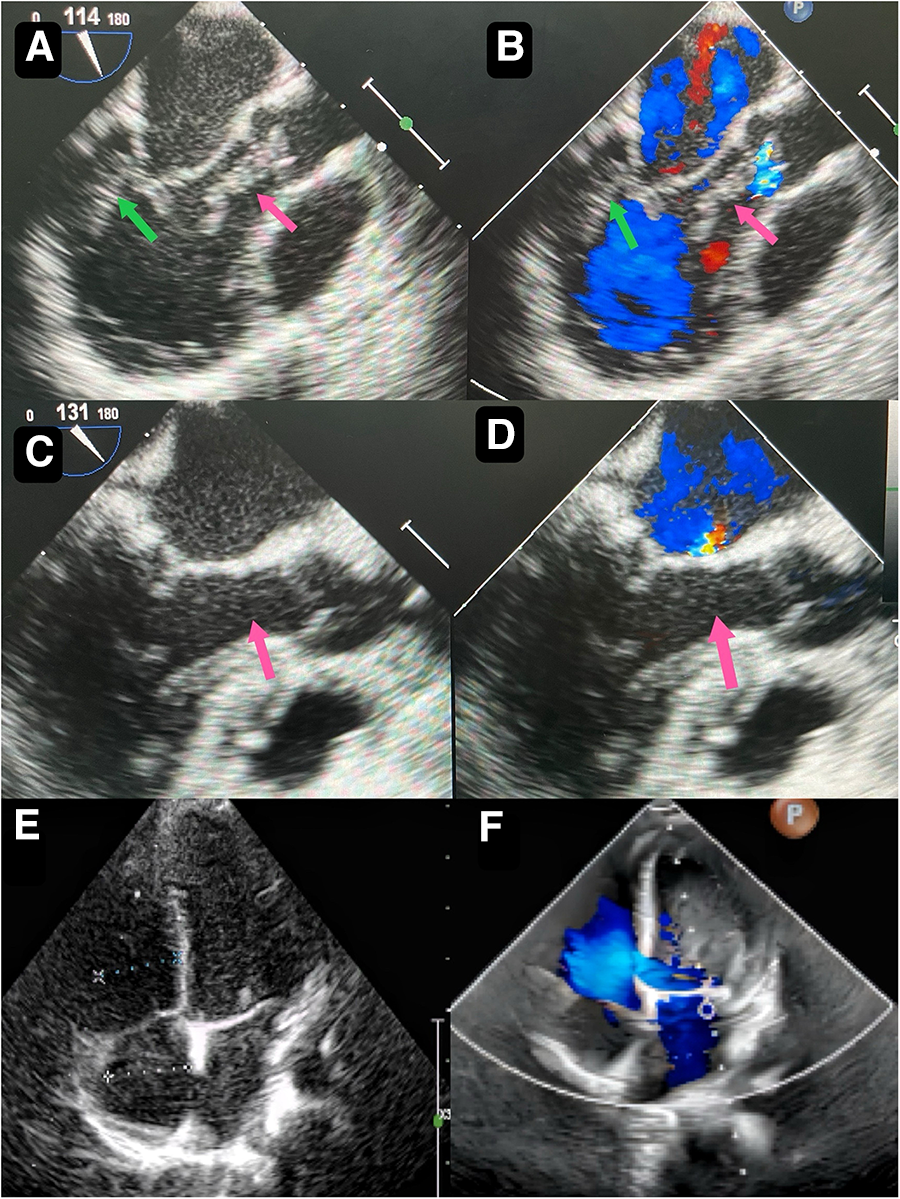

A 2-year-and-8-month-old toddler was admitted to the hospital for evaluation of chronic constipation attributed to long-standing low-fiber diet and poor therapeutic effect of prolonged lactulose use on softening stools. A heart murmur was noted on physical examination. The child had no relevant medical history or signs of infection, trauma, cold, or any other predisposing factors. Preoperative transthoracic echocardiography revealed a hyperechoic, approximately 32 mm by 16 mm mass in the posterior wall of the left ventricle (Figure 1A). In addition, an echogenic “string of beads” was observed wiggling in the left ventricular outflow tract, with one end connected to the posterior part of the left ventricle and the other end appearing to be connected to the left coronary sinus of the aorta (Figure 1B). The sizes of the four chambers were considered normal, and the ejection fraction was 63%. Interestingly, this child showed no clinical symptoms and results of coagulation assays, neutrophil, C-reactive protein, complete antinuclear antibody, antineutrophil cytoplasmic antibodies, and antistreptolysin O titer tests were all insignificant. A diagnosis of tumor, thrombus or vegetation was yet to be made.

Figure 1

Preoperative transthoracic echocardiography reveals a slightly hyperechoic, approximately 32 mm by 16 mm mass in the posterior wall of the left ventricle (A) echogenic “string of beads” is observed wiggling in the left ventricular outflow tract, with one end connected to the posterior part of the left ventricle and the other end appearing to be connected to the left coronary sinus of the aorta (B) postoperative transesophageal echocardiogram shows complete removal of the mass (C) postoperative transesophageal echocardiogram shows competent mitral valve (D) preoperative transthoracic echocardiogram shows competent mitral valve (E) postoperative transthoracic echocardiogram mitral valve shows trivial regurgitation (F).

Though the child was generally doing well and hemodynamics stable, there remained a concerning risk that the string part may break off and result in embolism. After careful consideration and discussion in a multidisciplinary team, surgical excision was planned. During the procedure, an incision was made in posterior leaflet of the mitral valve to expose the mass. It was shown that part of the mass was like a string of beads (Figure 2A), while the other part was embedded in the posterior left ventricular wall, close to the posterolateral papillary muscle (Figure 2B). The mass was predominantly white, with an intact capsule and a tough texture. After successful removal of the mass, water injection test showed significant regurgitation of the mitral valve from anterior leaflet prolapse. Mitral valve repair was performed. The ascending aortotomy was performed to exclude any residual mass in the aorta, though there was no residual mass found. Postoperative transesophageal echocardiogram showed complete removal of the mass (Figure 1C) and competent mitral valve (Figure 1D). Subsequent histopathological analysis confirmed the mass as a cardiac fibroma with myxoid degeneration (Figure 3). The results of the immunohistochemical analysis of the heart tumor specimen was as follows: Ki-67(10%+), DES (+), SMA (+), CR (focal +), CD34 (vascular +), Vim (+), EMA (−), CK (−), CD163 (+), ALK (−). The recovery was uneventful and the patient was discharged on postoperative day 10. Upon Follow-up, investigations including chest radiogram and electrocardiogram revealed no significant abnormalities. Transthoracic echocardiography demonstrated mild hyperechogenicity of the left ventricular papillary muscles, potentially related to postoperative changes. There was trivial regurgitation of the mitral valve (Figure 1F). Left ventricular systolic function was preserved. The patient's family reported no issues with daily activities or exercise tolerance.